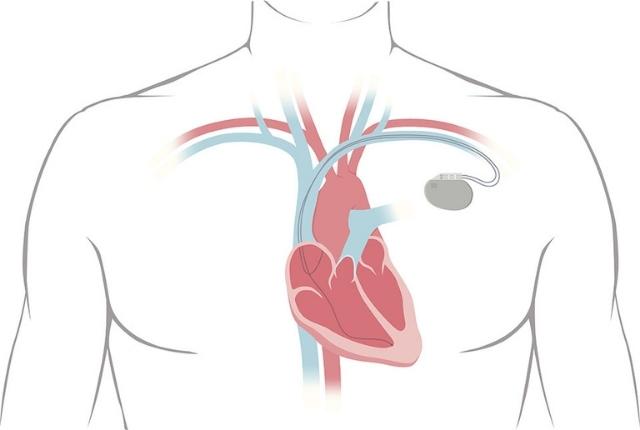

Un pacemaker, également appelé stimulateur cardiaque ou pile cardiaque, est, comme son nom l'indique, un dispositif médical implanté dans le corps humain ayant pour but de délivrer des impulsions électriques régulières au myocarde (tissu musculaire du cœur) et de stimuler ainsi les contractions des muscles à un rythme régulier. Il peut délivrer une impulsion électrique pendant plusieurs années grâce à une batterie. Ce pacemaker pour le cœur habituellement implanté sous la clavicule est donc utile pour surveiller l'activité cardiaque naturelle, ainsi que pour traiter les troubles du rythme cardiaque (arythmie cardiaque) , tels que la bradycardie par exemple (fréquence cardiaque anormalement lente), et leurs conséquences.

Un pacemaker cardiaque est un appareil composé d'un boîtier d'environ 4 centimètres – contenant notamment la batterie – et de sondes reliant le boîtier aux cavités cardiaques. L'implantation d'un pacemaker est généralement réalisée sous anesthésie locale et ne nécessite donc pas d'opération à cœur ouvert.

Un pacemaker ou stimulateur cardiaque implanté sous la clavicule surveille le cœur du patient et l'aide à battre à une fréquence normale et régulière, en stimulant les contractions musculaires.

L'implantation d'un stimulateur cardiaque est souvent réalisée sous anesthésie locale, voire générale, et ne requiert donc généralement pas d'opération à cœur ouvert. Elle consiste en une incision en haut de la poitrine, sous la clavicule, et ce afin d'insérer les sondes jusqu'aux cavités cardiaques, puis le boîtier contenant notamment la batterie.